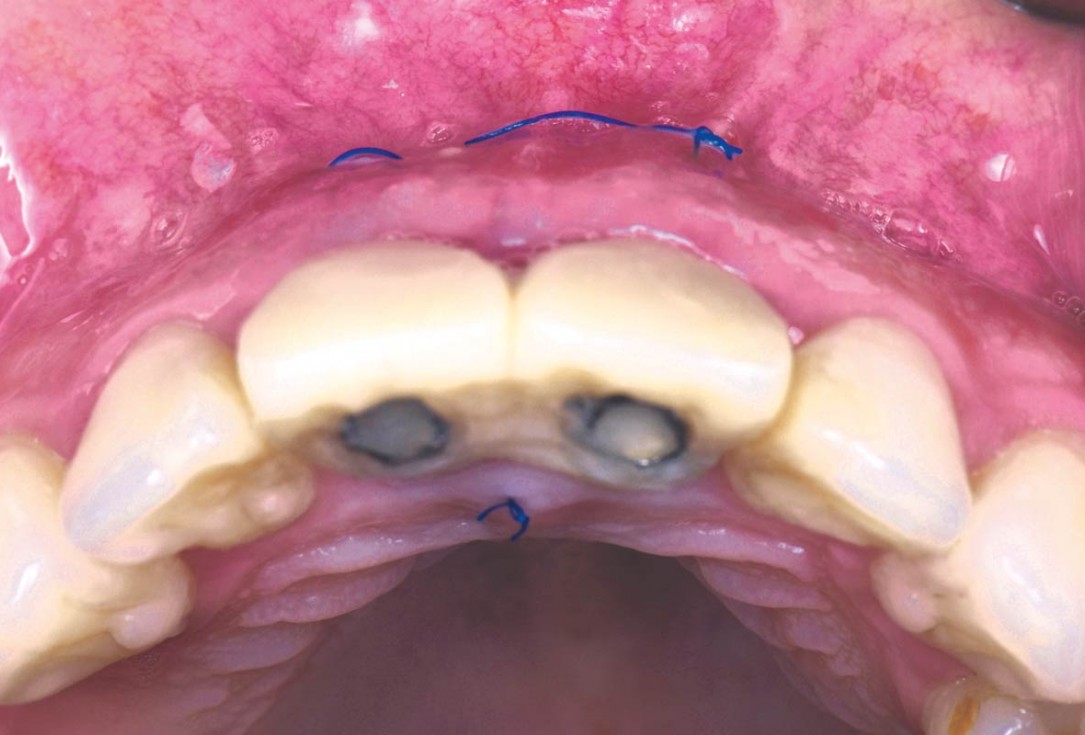

06/22 - To improve the soft tissues, two folded mucoderm® are placedcerabone® and mucoderm® for immediate implantation in the aesthetic area - Dr. D. Robles

07/22 - To achieve greater volume, mucoderm® are placed through an envelope and sutured apicallycerabone® and mucoderm® for immediate implantation in the aesthetic area - Dr. D. Robles

08/22 - To achieve greater volume, mucoderm® are placed through an envelope and sutured apicallycerabone® and mucoderm® for immediate implantation in the aesthetic area - Dr. D. Robles